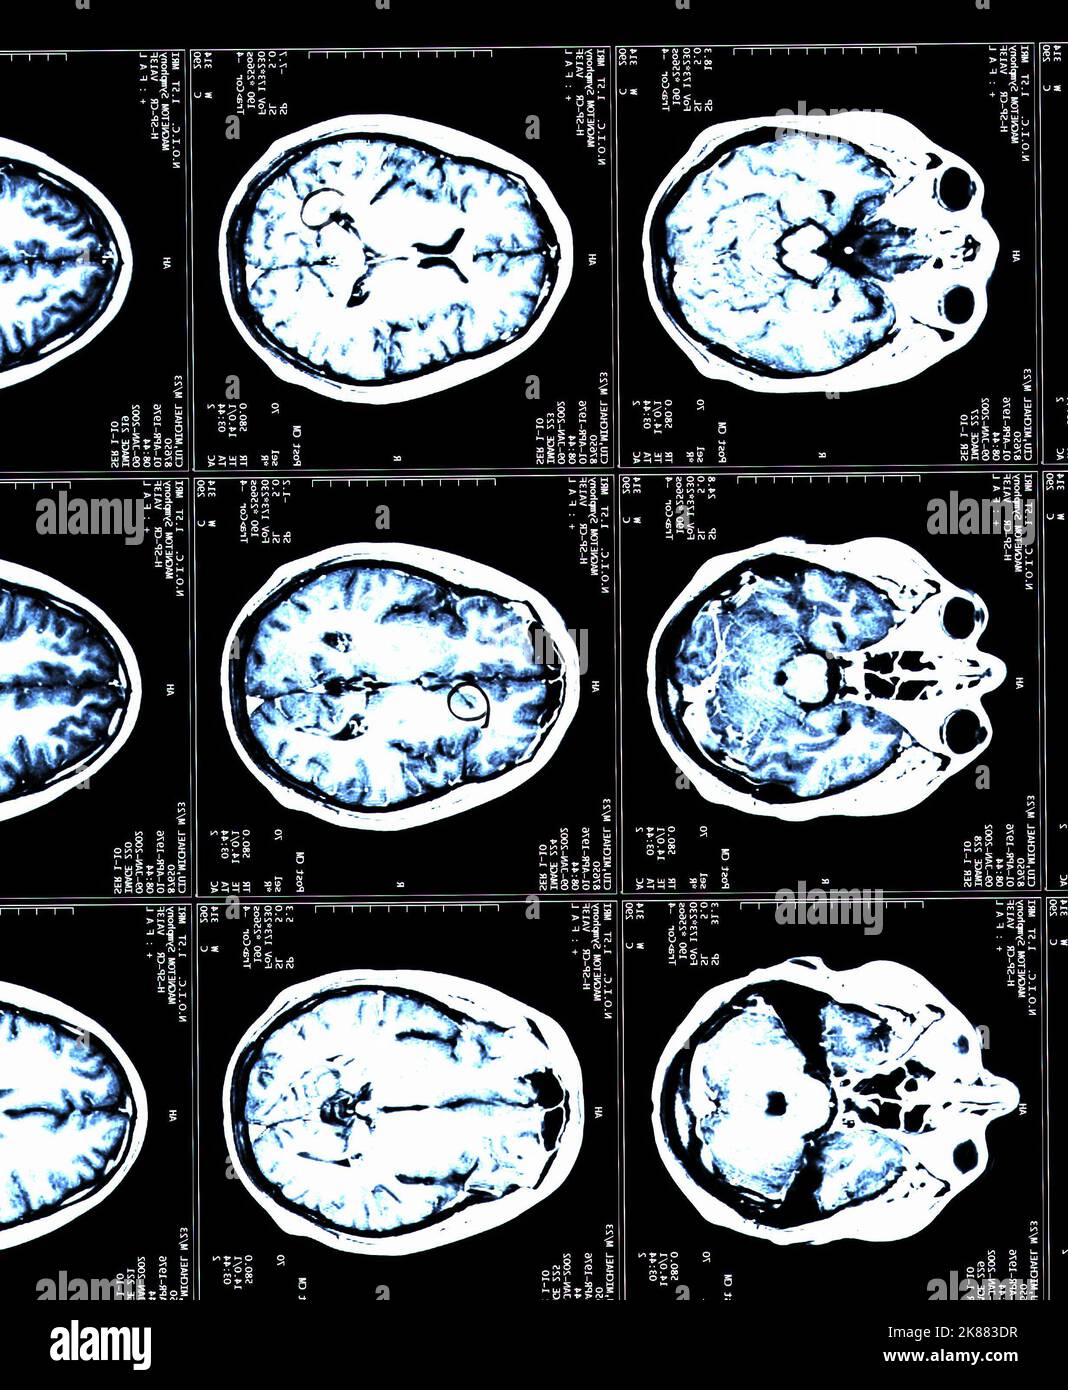

Can Ms Be Seen In Brain Mri . The number of lesions on an initial mri of the brain (or spinal cord) can help assess your risk of developing a second attack in the future and. A doctor may diagnose you with ms if they can see. So, what's happening here and what should someone do? Advanced imaging of the brain and spinal cord is a critical tool in diagnosing ms. The appearance of demyelination is often described as lesions. If you have multiple sclerosis (ms), odds are that lesions (abnormal areas or changes such as plaques or scarring caused by disease or injury in a tissue or organ) will. Mri and ct scans are the primary imaging tests used to help diagnose ms. Doctors may also use a type of scan called flair,. Lesions in the brain and spine appear as lighter or darker spots that appear different from normal tissue. You can see some of the demyelination with magnetic resonance imaging (mri). Though the vast majority of ms patients have abnormalities on brain mri, an estimated 5% of patients have normal imaging.

Advanced imaging of the brain and spinal cord is a critical tool in diagnosing ms. The appearance of demyelination is often described as lesions. A doctor may diagnose you with ms if they can see. Though the vast majority of ms patients have abnormalities on brain mri, an estimated 5% of patients have normal imaging. If you have multiple sclerosis (ms), odds are that lesions (abnormal areas or changes such as plaques or scarring caused by disease or injury in a tissue or organ) will. Doctors may also use a type of scan called flair,. The number of lesions on an initial mri of the brain (or spinal cord) can help assess your risk of developing a second attack in the future and. So, what's happening here and what should someone do? You can see some of the demyelination with magnetic resonance imaging (mri). Lesions in the brain and spine appear as lighter or darker spots that appear different from normal tissue.